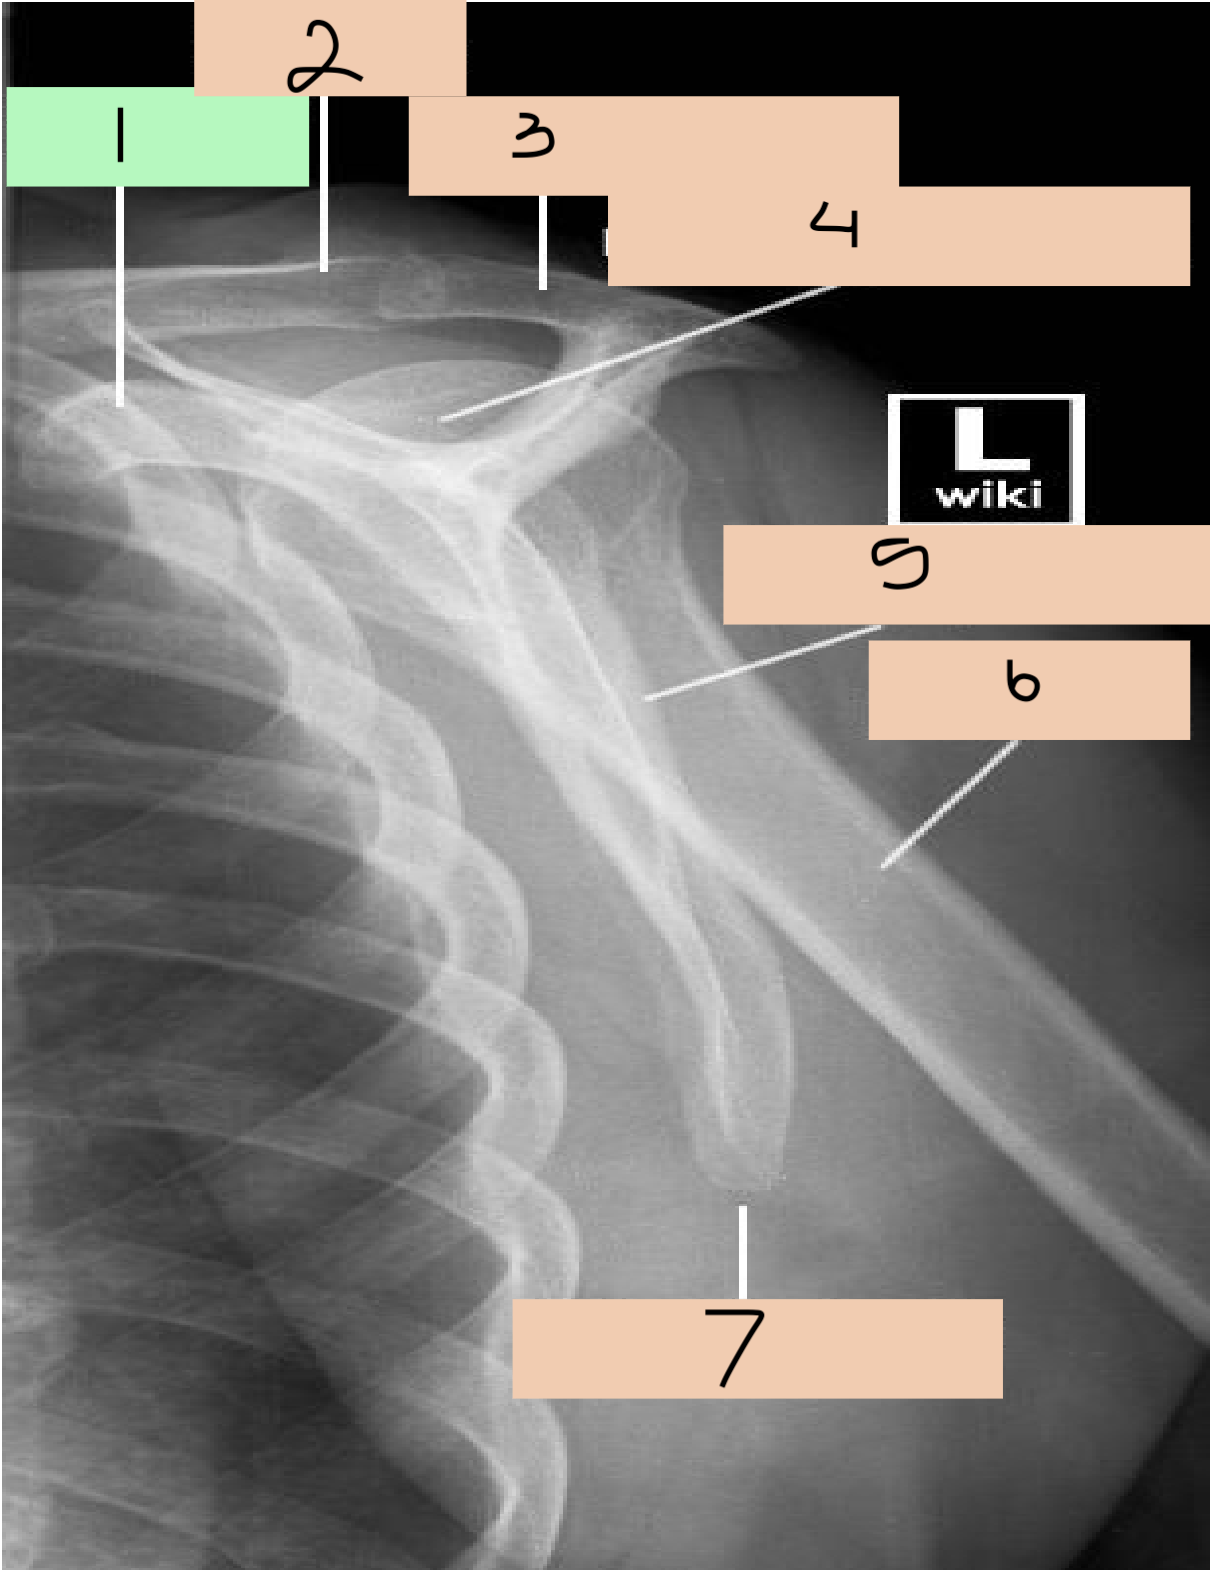

1

coracoid process

2

clavicle

3

acromian

4

head of humerus

5

lateral border scapula

6

shaft of humerus

7

inferior angle scapula